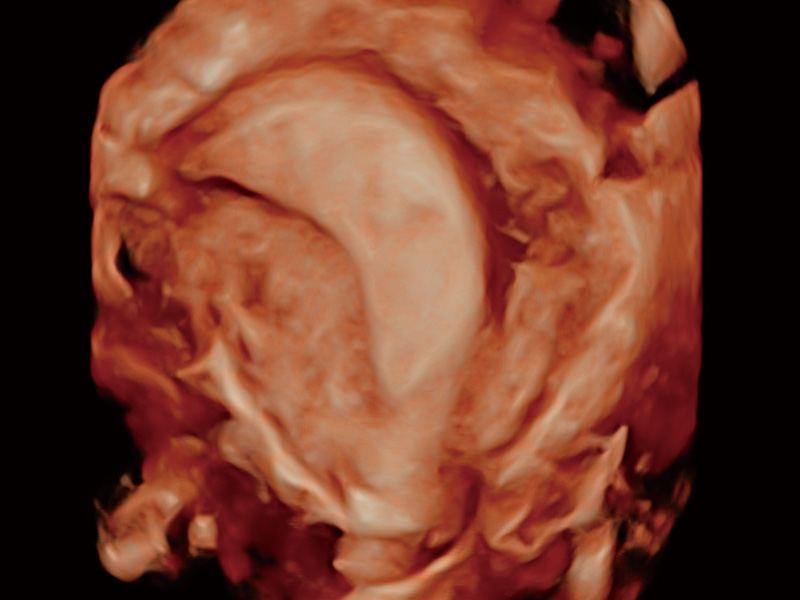

腔内容积探头

腔内三维成像技术获得显著提升,超大扇角在满足日常基础扫查的同时,支持卵泡自动测量及多种三维渲染模式,为您提供更多的诊断信息,尤其是在子宫畸形的诊断,内膜及肿瘤占位观测中起到了重要的作用。

临床图

单角子宫